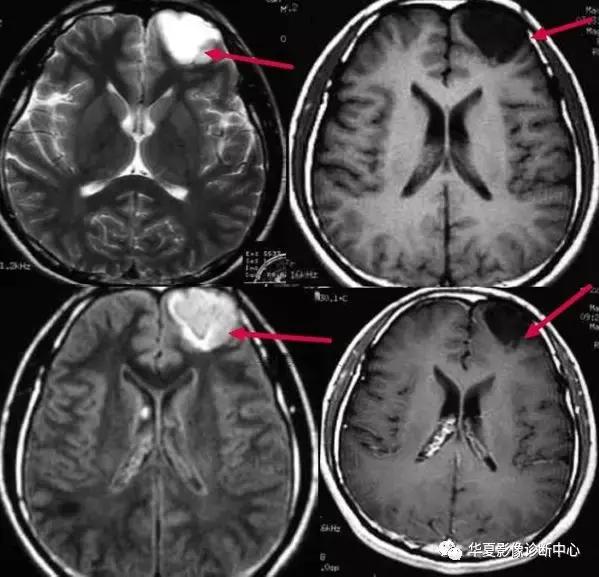

十三、空三角征:

在CT或MRI增强图像上,在多个连续的横断CT或MRI图像上表现为上矢状窦三角形增强或高密度区域内出现相对低密度区。空三角征为矢状窦血栓形成时颅脑增强CT或MRI的常见征象,出现率约为35%,表现为强化的三角形环即中心低信号周边为三角形高信号,位于上矢状窦区。矢状窦邻近有血管丛,为血栓形成后的侧支循环。目前对该征病理生理的解释并不一致,包括以下假说:1)静脉窦内血栓再通。2)栓子机化。3)血脑屏障破坏。4)硬膜外和硬膜侧支静脉的扩张。有认为最合理的解释为硬膜血管的强化,为所在区域的血管网(硬膜海绵间隙)和脑膜静脉属支的强化,中心低密度为栓子。国外学者认为血栓形成的主要原因有3个:1)血管易于血栓形成,包括原发性和遗传性疾病。最常见为继发性凝血酶原激活如妊娠;血液或系统性疾病如红细胞增生症、系统性红斑狼疮、恶性肿瘤、脱水导致血液浓缩,药物如避孕药或化疗药如L一天门冬酸胺酶。2)血流障碍如肿瘤、心衰、动静脉痊。3)静脉窦壁的炎症、感染、纤维化或损伤,如:静脉窦炎、外耳炎、乳腺炎和创伤。l/4的病人查不到原因。矢状窦血栓形成的临床表现有头痛、视乳头水肿等。急性脑静脉窦血栓形成往往存在比较典型的表现,可见上矢状窦区三角形以及横窦区条索状高密度影,是脑静脉窦内新形成血栓病变早期的直接折射;临床上虽然脑硬膜窦血栓的发病率较高,不过单纯大脑浅静脉及深静脉部位的血栓形成较少;CT增强显示空三角征或条状充盈缺损,特征明显,对急性和亚急性患者有重要意义。CT平扫亦可显示由于静脉淤血、静脉性脑梗死以及脑脊液重吸收障碍引起的病理征象,如对称或弥漫性脑肿胀、多灶性脑出血等。

MRI平扫对本病较为敏感,可显示不同时期血栓的信号,而正常静脉窦的留空信号则消失。急性期T1WI为等信号,与留空信号较为接近,T2WI为低信号,由于信号特征较不明显,因此MRI不易诊断;亚急性期T1WI、T2WI均为明显高信号,容易确诊;慢性期各脉冲序列血栓信号减低,常常出现假阳性。但是可通过与CVST引发的脑水肿、脑梗死、脑积水等间接征象相结合,以辅助诊断。